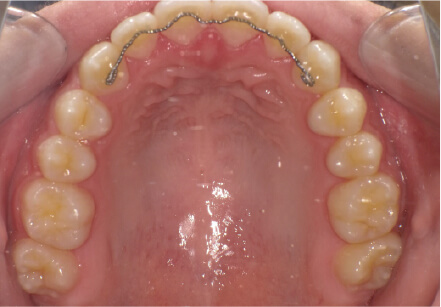

叢生の症例

9歳

/

女性

相談内容

マイオスマイルからの移行

カウンセリング・診断結果

上11捻転、上33スペース不足、インビザで歯列矯正

治療内容・方法

全額アライナー矯正 クリアコレクト

術後の経過・現在の様子

リンガルアーチ使用

治療のリスク

痛み・歯根吸収・歯肉退縮・虫歯・後戻り

費用・治療期間

(マウスピース矯正のみ)440,000円+220,000円 月々27,500円、9ヶ月+myo1年10ヶ

トレーニングなど